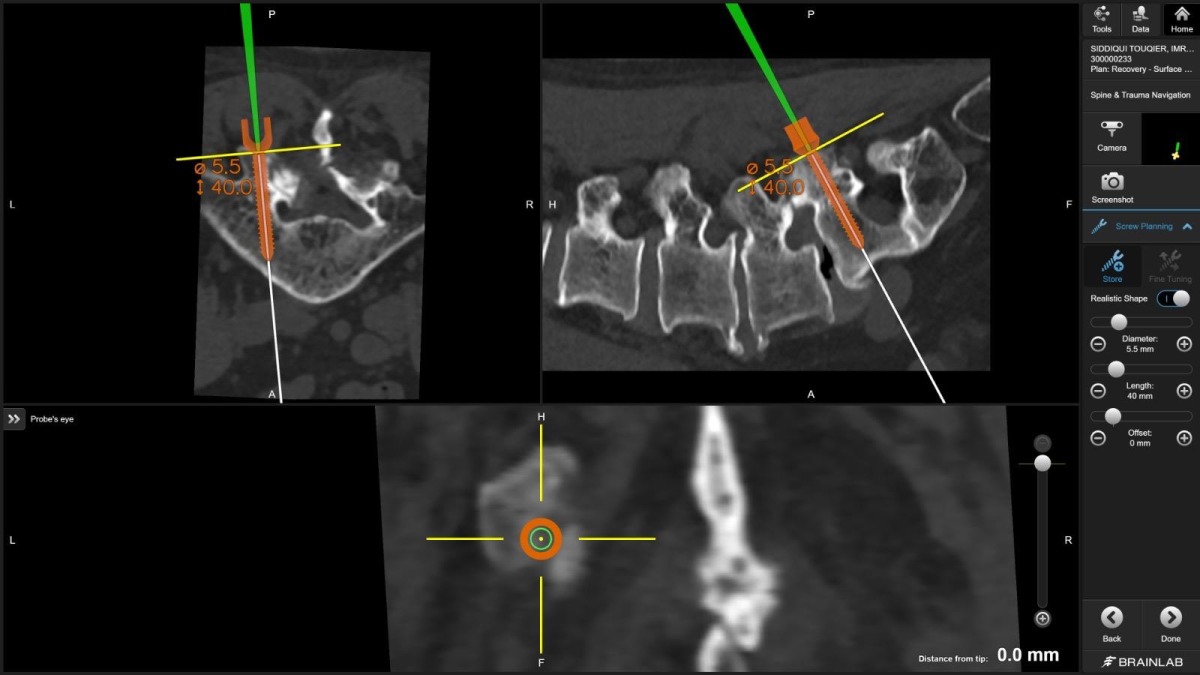

"For the first time in Qatar, I used virtual reality technology to plan spine screws before surgery," Dr. Belkhair explains. "These electronic glasses showed me 3D images of the patient's CT scan, allowing me to plan screw placement in the perfect position. What I saw in those glasses translated directly into the operating room, visible on screens, guiding every movement."

Dr. Belkhair took this further. Before the patient entered the operating room, he used virtual reality glasses that transformed CT scan data into an immersive, three-dimensional surgical rehearsal space. He could rotate the spine, zoom into pedicles (the narrow bone corridors where screws must pass), measure angles, and plan screw trajectories with unprecedented detail.

"The planning became the roadmap. The navigation ensured we followed it perfectly," he notes.

Dr. Belkhair's integration of VR planning with intraoperative navigation creates a seamless workflow: plan in virtual space, execute with real-time guidance, verify with immediate imaging.

"The glasses showed me the patient's spine as if I could hold it in my hands," Dr. Belkhair describes. "I could see where every screw needed to go, what angle, what depth. It's surgical precision at a level we couldn't achieve even five years ago."